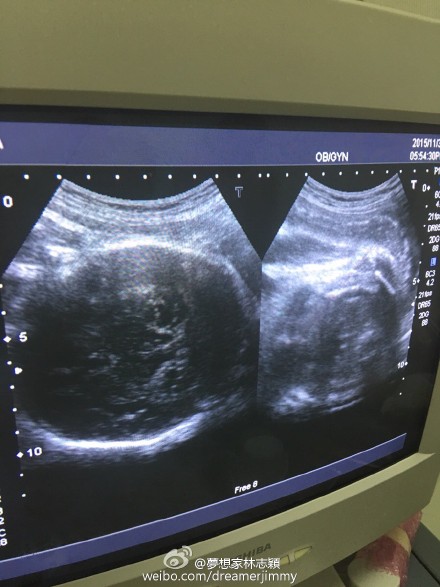

11月30日晚,林志穎通過(guò)微博曬出老婆的B超照,并給大家報(bào)平安,寫道:“陪老婆產(chǎn)檢,baby很健康!”

林志穎曬雙胞胎B超照

新浪娛樂(lè)訊 11月30日晚,林志穎通過(guò)微博曬出老婆的B超照,并給大家報(bào)平安,寫道:“陪老婆產(chǎn)檢,baby很健康!”此微博曝光后,網(wǎng)友紛紛留言囑咐要好好照顧老婆和兒子。

早前,林志穎為了慶祝微博粉絲破六千萬(wàn),公布妻子懷孕喜訊,并透露是雙胞胎,預(yù)產(chǎn)期是在12月,會(huì)在臺(tái)灣剖腹生產(chǎn)。近日,林志穎在微博曬快餐店的自拍照,透露是為孕妻買夜宵,并稱老婆特別能吃。(我是彌爾)